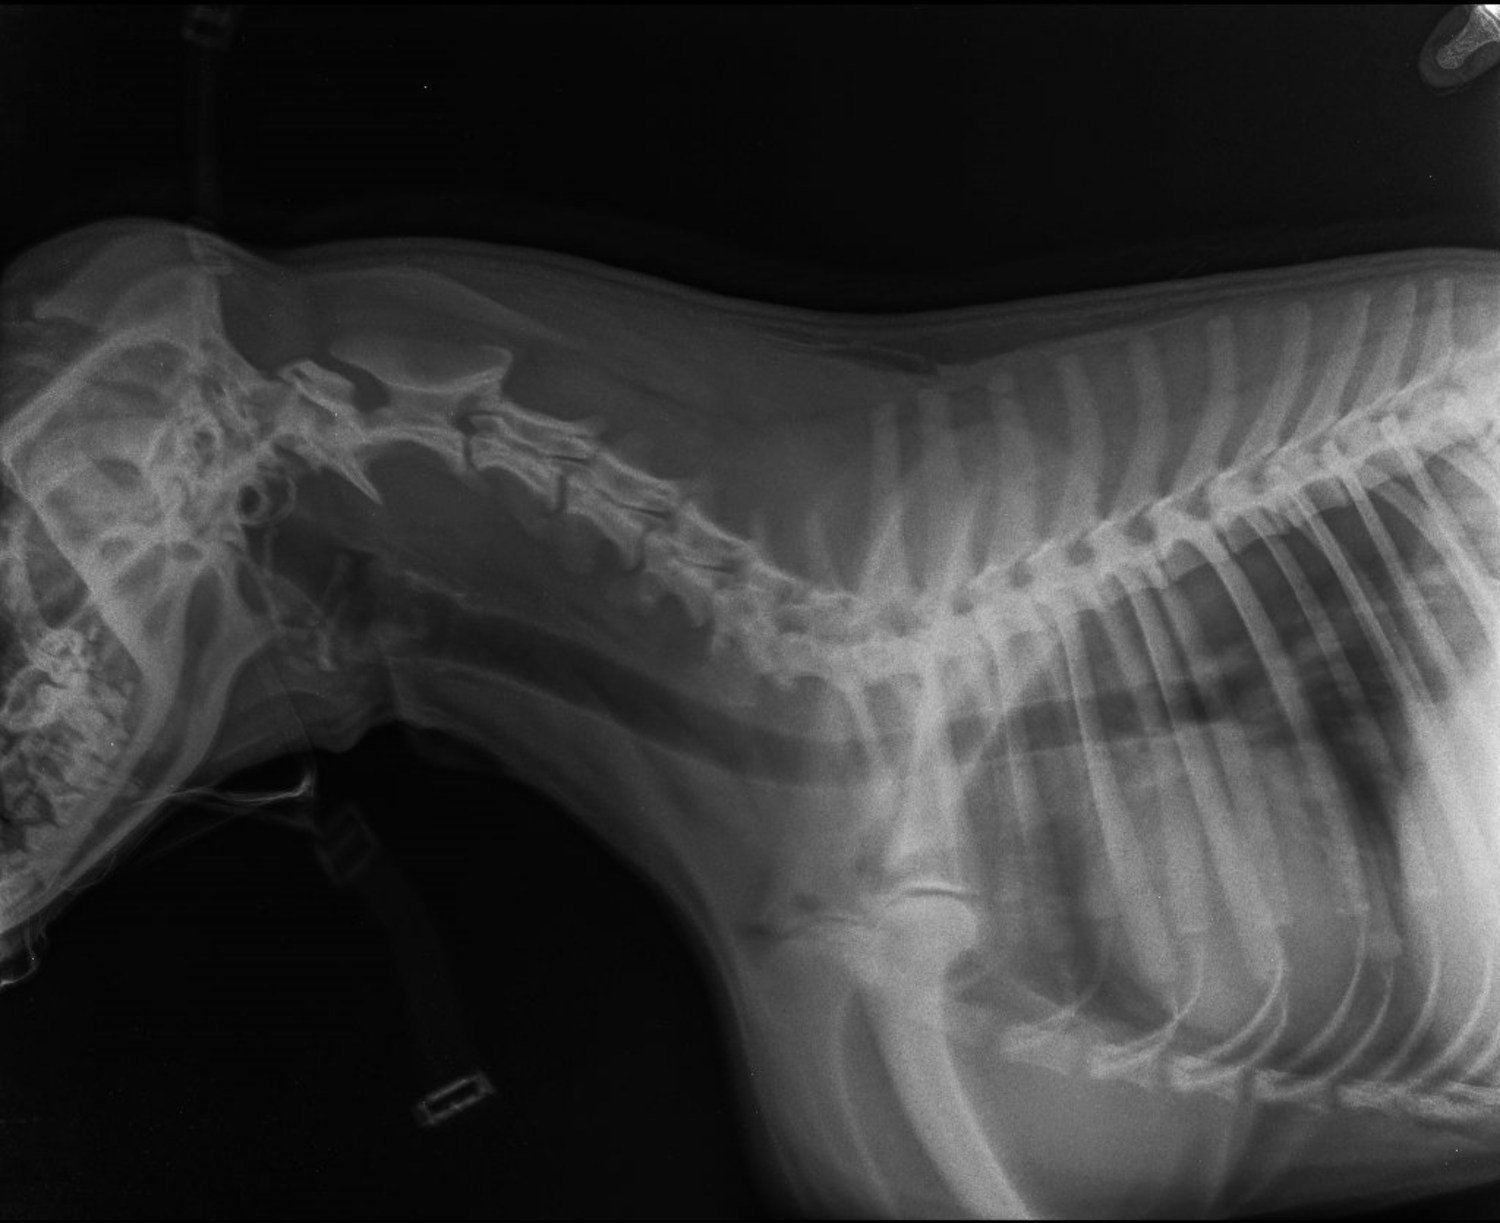

動物病院に連れて行き、レントゲン写真を撮ってもらったところ、予想が的中。スモーキーの胃の中に、はっきりと指輪の影が写っていた。

ジュリーさんは「スモーキーは本当におバカさん。ママの婚約指輪を食べちゃった。吐き戻さなかったから、ママがウンチの中を探す羽目に」と投稿文を添えて、レントゲンと出てきた指輪の写真を投稿した。